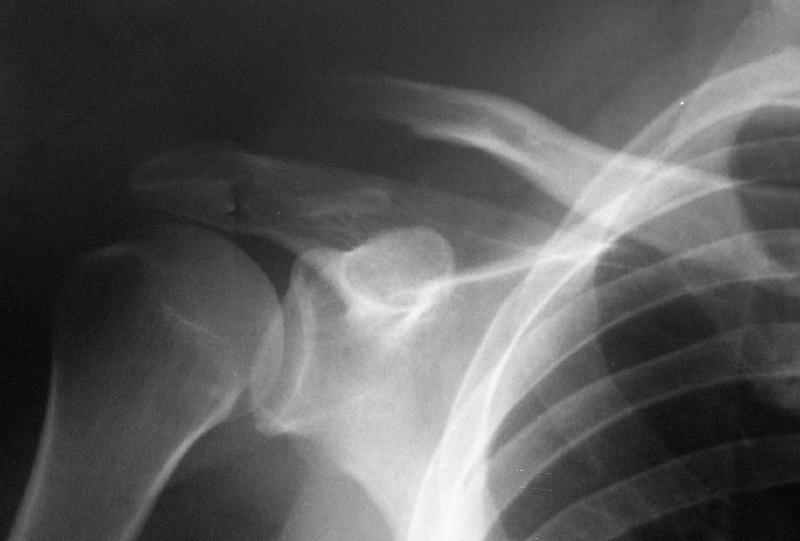

"Толкатель" - укороченная спица с упором. На первичных снимках - оскольчатый перелом, отдельный фрагмент с местом прикрепления кл-кл связки сместился каудально.

Первично правильно сопоставленный перелом (небольшой разрез, спицы) привел бы к тому, что костный фрагмент, отрванный ключично-клювовидной связкой, лег аккурат под своим ложем и тесно к нему... то бишь в итоге сросся бы без проблем... (кстати на вашем снимке костный фрагмент "оскольчатого перелома" консолидирован... то есть даже достигнутая вами несостоятельная фиксация привела к приростанию авульзионно оторванного

фрагмента)

То, что было представлено на вашем снимке - ... - создается впечатление что никакой консолидации в области перелома (основного) достигнуто не было...

АПК> На первичных снимках -

АПК> оскольчатый перелом, отдельный фрагмент с местом прикрепления кл-кл

АПК> связки сместился каудально.

Я бы назвал данный перелом как перелом с костной авульзией ключично-клювовидной связи... Потому как данный фрагмент лежит вне основной зоны перелома...